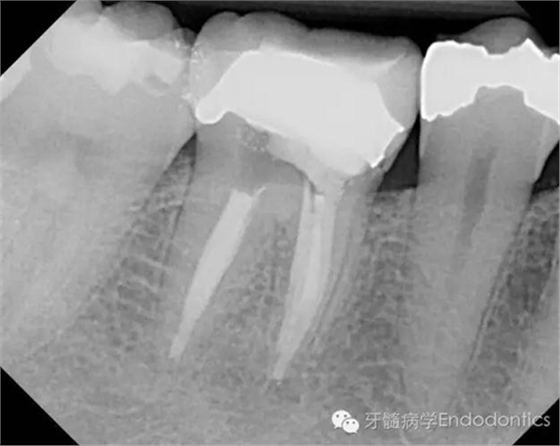

我決定對(duì)患牙行一次性根管再治療。我成功的取出了一根斷針和三根(其中兩根超出根尖)Thermofil(固核載體)。對(duì)所有根管進(jìn)行徹底的清理、成形,干燥后使用熱牙膠垂直加壓技術(shù)完成充填。

兩年后復(fù)診,病變愈合。

圖5.根充后X線片

圖6.隨訪兩年后X線片